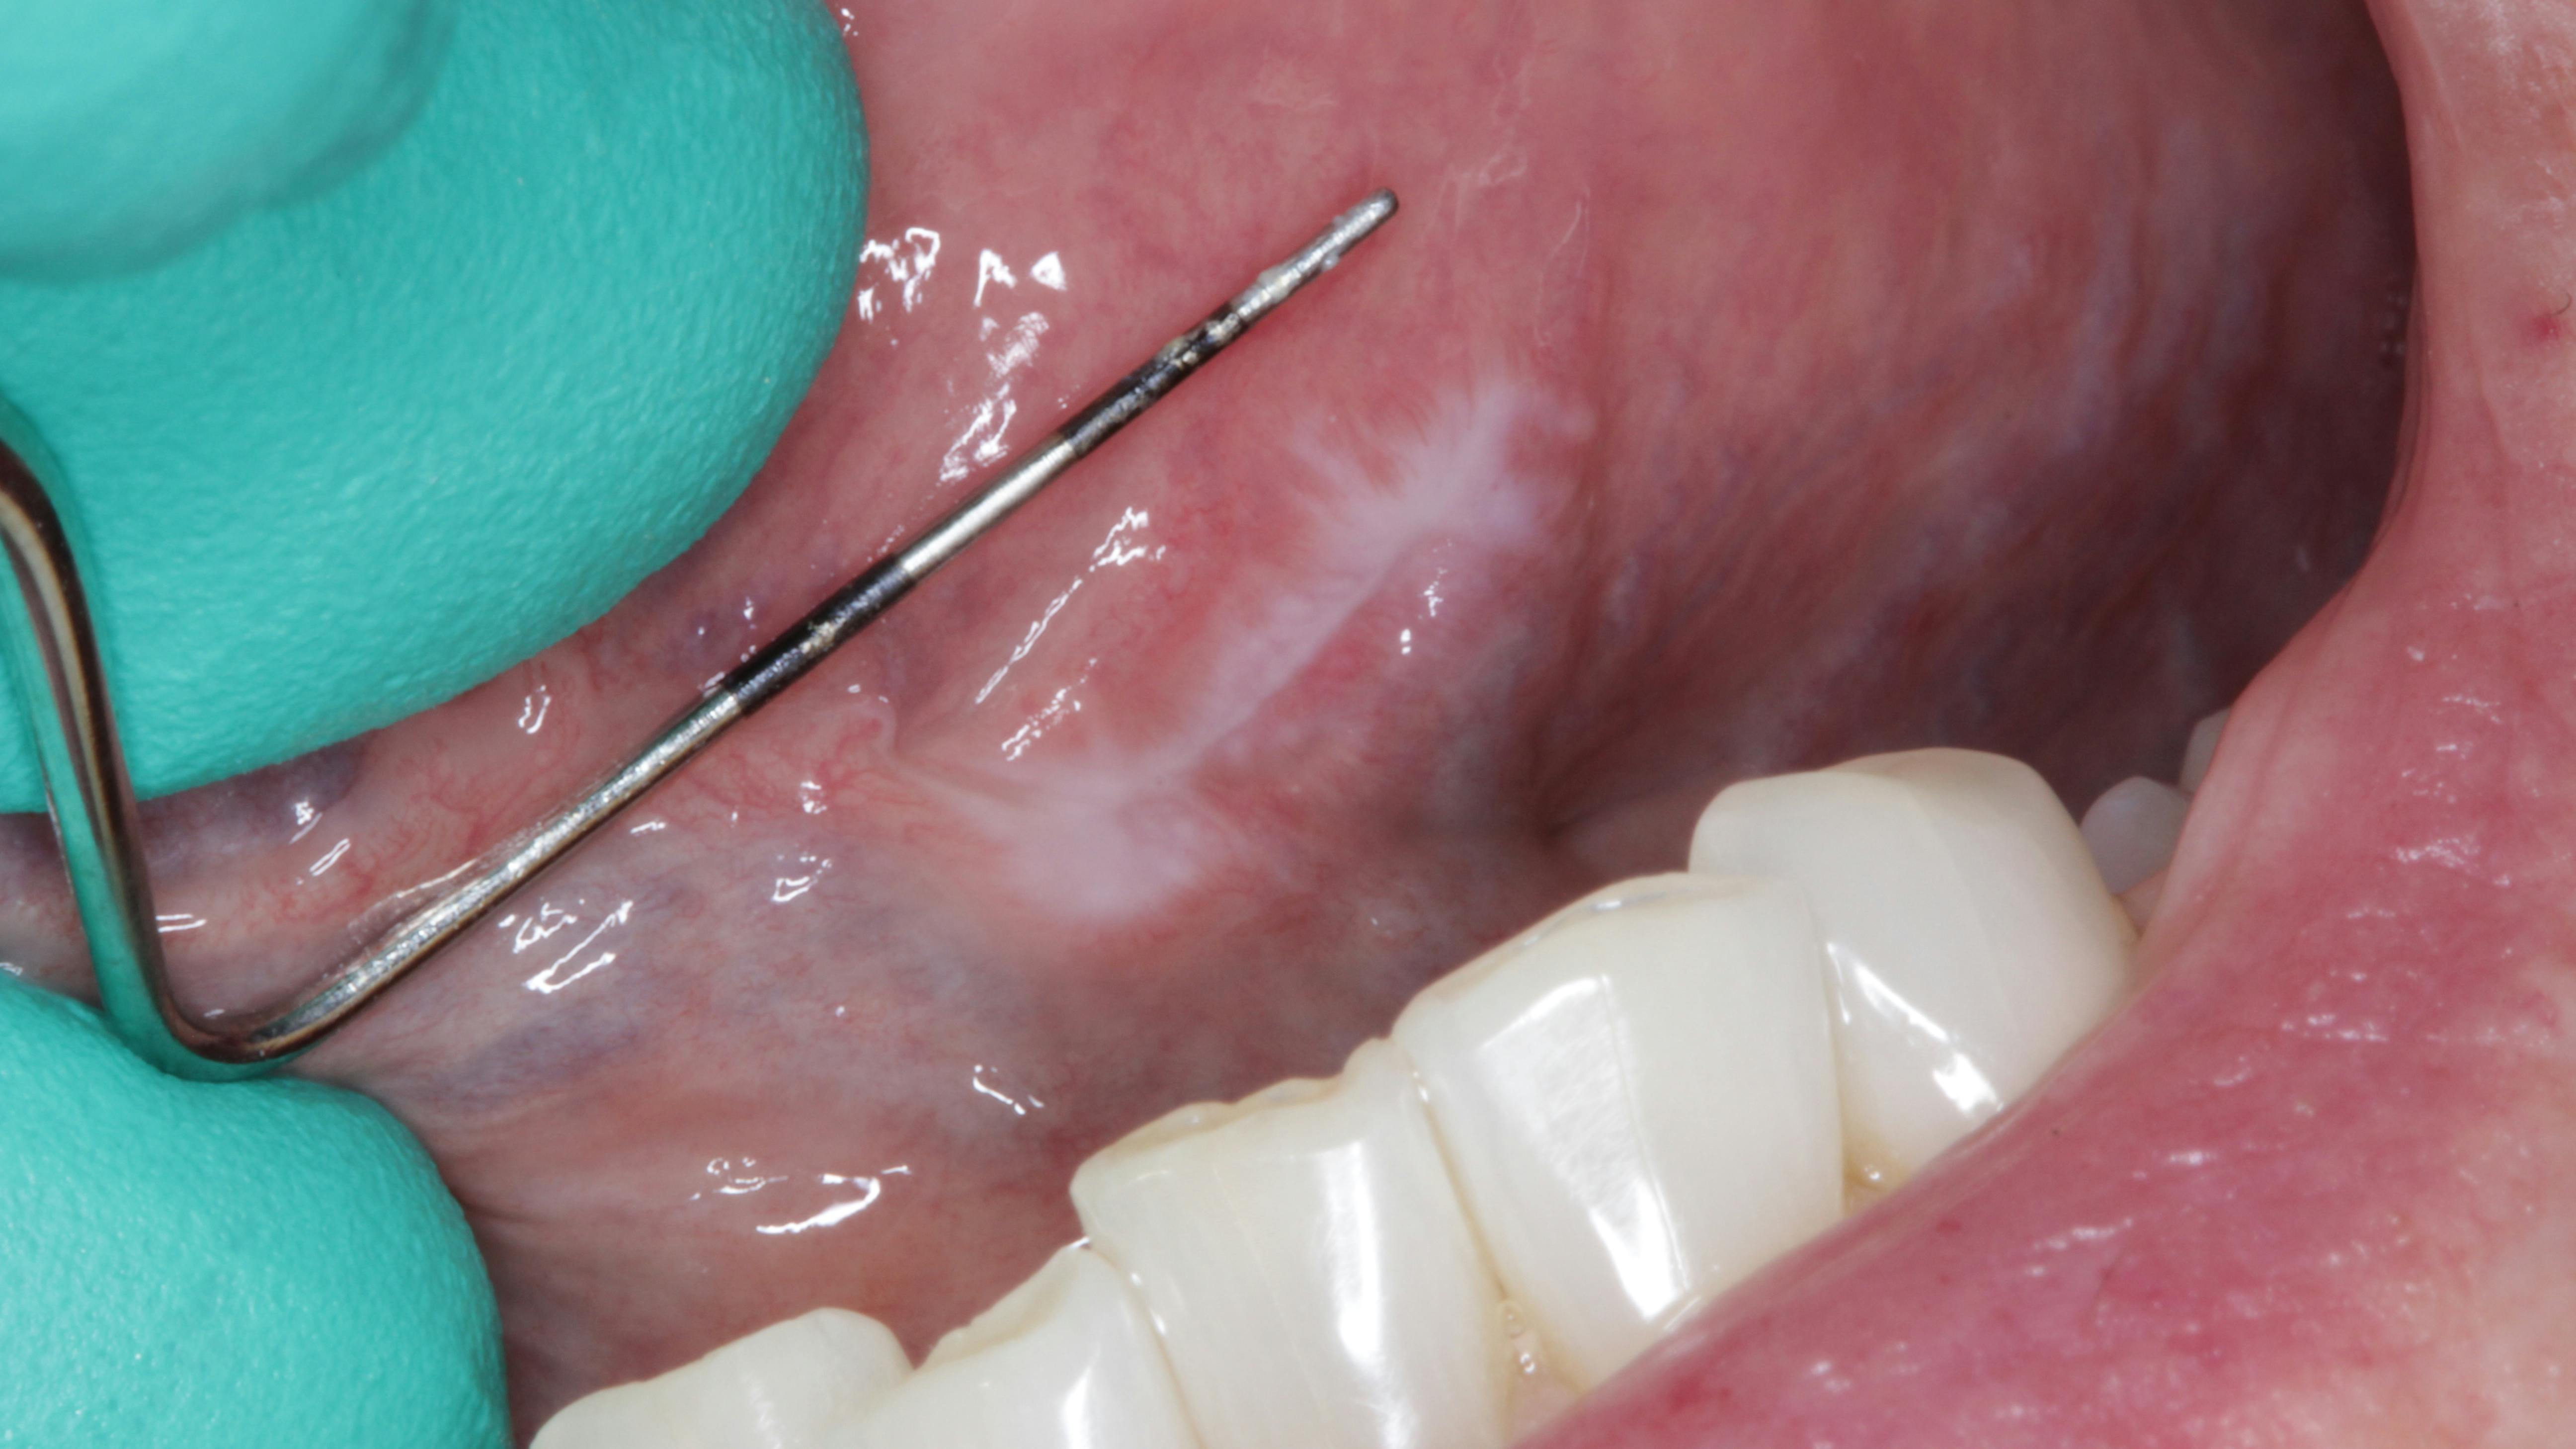

Patient: 62-year-old female

- 9 mm x 3 mm white leukoplakic patch of tissue on left ventral surface of the tongue

- Patient was unaware of its presence

- Not tender to palpation and could not be scraped off

- Noncontributory health history (patient was taking vitamin D supplements)